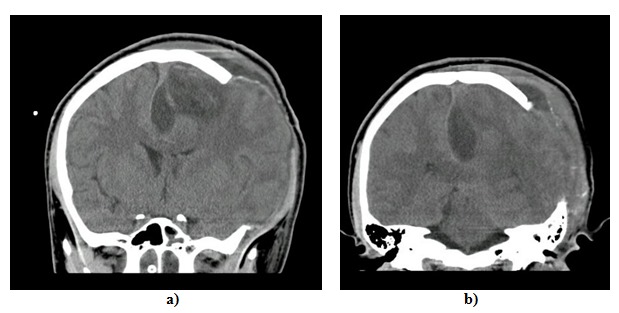

Se pasó un catéter ventricular en dos pasos con posterior exteriorización y conexión a un sistema de monitoría y drenaje. Se tomó presión intracraneal que se reportó en 40 mm Hg con posterior mejoría del diámetro pupilar (ojo derecho: 2 mm; ojo izquierdo: 3 mm). Previo al egreso del quirófano se revaloraron las pupilas, que presentaban una dilatación de 2 mm en el ojo derecho y de 5 mm en el ojo izquierdo no reactiva, que no se resolvió a pesar del paso de bolo de manitol, por lo que se consideró una craniectomía descompresiva izquierda (figura 3). Se realizó la apertura y disección del músculo temporal con rechazo del colgajo musculocutáneo hacia inferior. Se realizó craneotomía de 12 × 11 cm con fresa y cuchilla de midas rex y ampliación hacia la fosa media con gubia.

Al tercer día de la cirugía presentó picos febriles hasta de 39 ºC y se reportaron exámenes paraclínicos con aumento de leucocitosis con neutrofilia (tabla 1). Paralelamente, se empezó el descenso de la sedoanalgesia haciendo posible la evaluación de reflejos de tallo, con reflejo carinal y corneano bilateral presente. Por la alteración clínica y paraclínica se decidió la toma de un TAC de control que evidenciaba aumento de la colección interhemisférica (figura 4), que se definió según un concepto de neurocirugía no candidato a manejo quirúrgico. Con el objetivo de definir el foco infeccioso, fue valorado por cirugía maxilofacial en contexto de un microrganismo descrito como flora normal de la cavidad oral. Se le tomó un TAC de cara que presentaba ocupación parcial del seno maxilar izquierdo sin hallazgos que sugirieran procesos infecciosos ontogénicos. El paciente continuó con distermias, por lo que infectología pediátrica amplió estudios con hemocultivos, urocultivos, cultivos de secreción orotraqueal y de línea arterial, así como estudios para determinar inmunodeficiencias de base con reporte de estudios para VIH no reactivos. Adicionalmente, se modificó el esquema antibiótico con la suspensión de ceftriaxona y metronidazol y adición de meropenem 2 g/8 h. Se determinó que el tratamiento debía continuar durante 8 semanas.